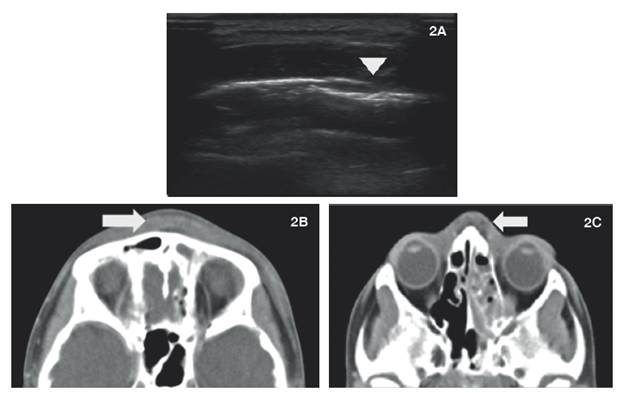

2A: La imagen ecográfica confirma engrosamiento de los tejidos blandos, asociado a colección liquida con septos finos en su interior y disrupción del hueso frontal (cabeza de flecha); 2B y 2C: Escanografia axial con medio de contraste de senos paranasales. Material con densidad de tejidos blandos, que ocupa celdillas etmoidales y seno frontal, con engrosamiento de tejidos blandos en región frontal y dorso nasal, asociado a colección liquida (flechas).

Figura 2: 2A: La imagen ecográfica confirma engrosamiento de los tejidos blandos, asociado a colección liquida con septos finos en su interior y disrupción del hueso frontal (cabeza de flecha); 2B y 2C: Escanografia axial con medio de contraste de senos paranasales. Material con densidad de tejidos blandos, que ocupa celdillas etmoidales y seno frontal, con engrosamiento de tejidos blandos en región frontal y dorso nasal, asociado a colección liquida (flechas).